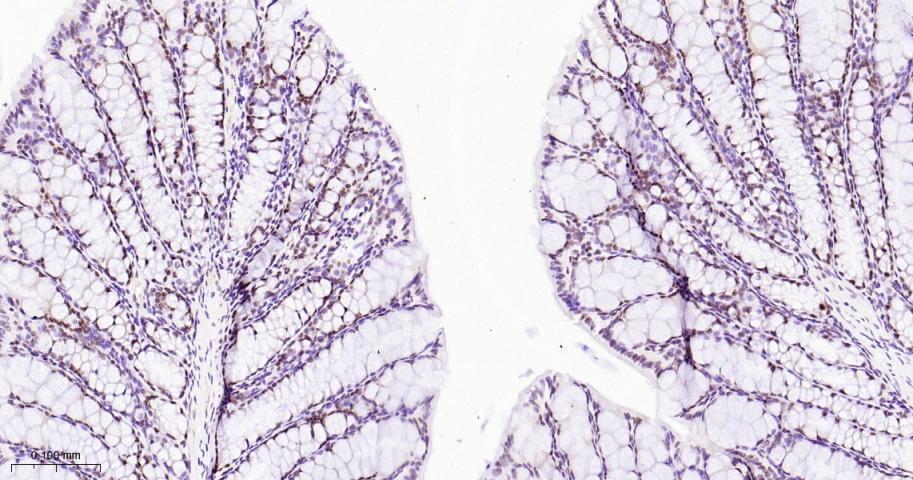

Paraformaldehyde-fixed, paraffin embedded Human Testicles; Antigen retrieval by boiling in sodium citrate buffer (pH6.0) for 15 min; The section was incubated with EHMT2 Monoclonal Antibody, Unconjugated (bsm-61806R) at 1:200 overnight at 4°C, followed by conjugation to the bs-0295G-HRP and DAB (C-0010) staining.